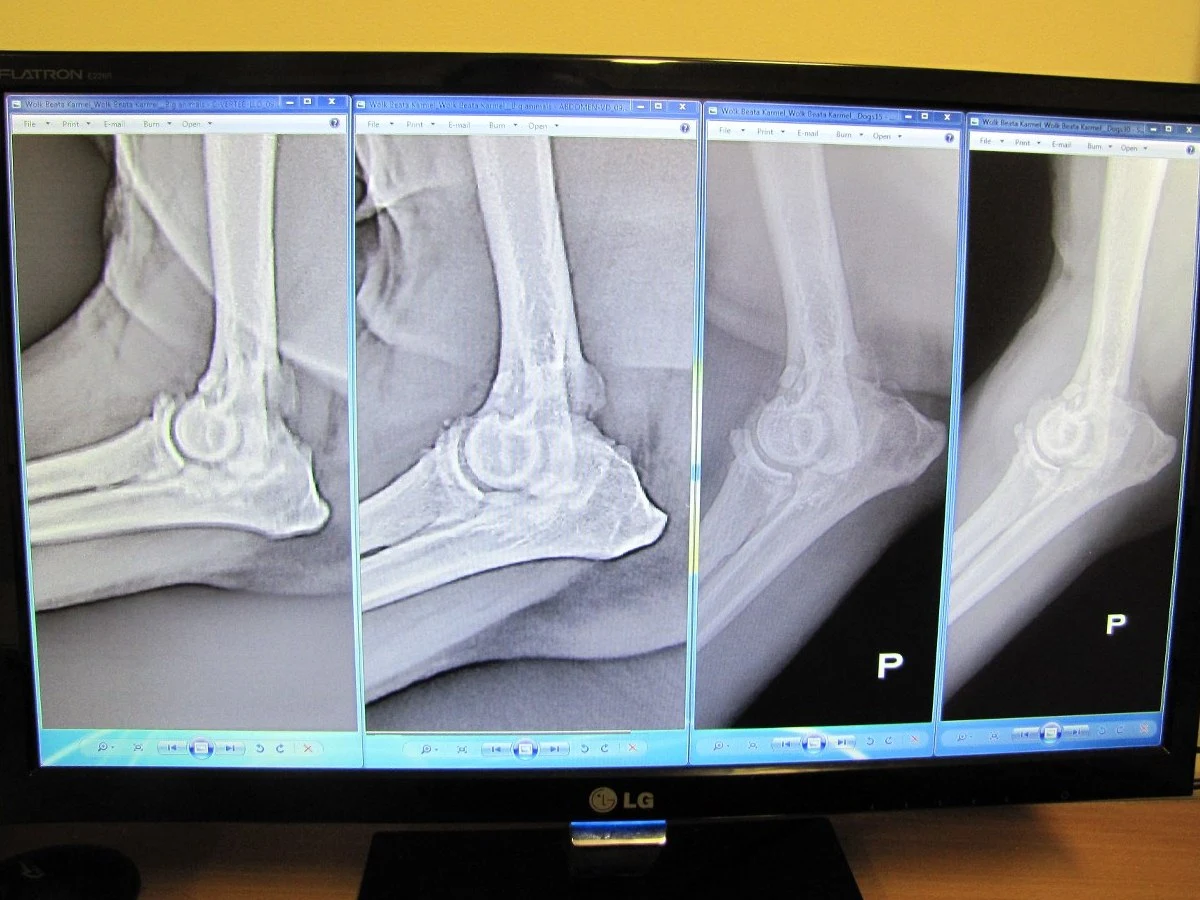

Po kilku dniach terapii pies już zaczął chodzić. Po dwóch tygodniach zaś, nie sprawiało mu to już najmniejszego bólu. Najnowsze zdjęcie RTG wykonane po 5 miesiącach potwierdza, że schorzenie całkowicie ustąpiło. To co widzimy na zdjęciu to obraz zupełnie zdrowego stawu - dodaje Sokołowski.